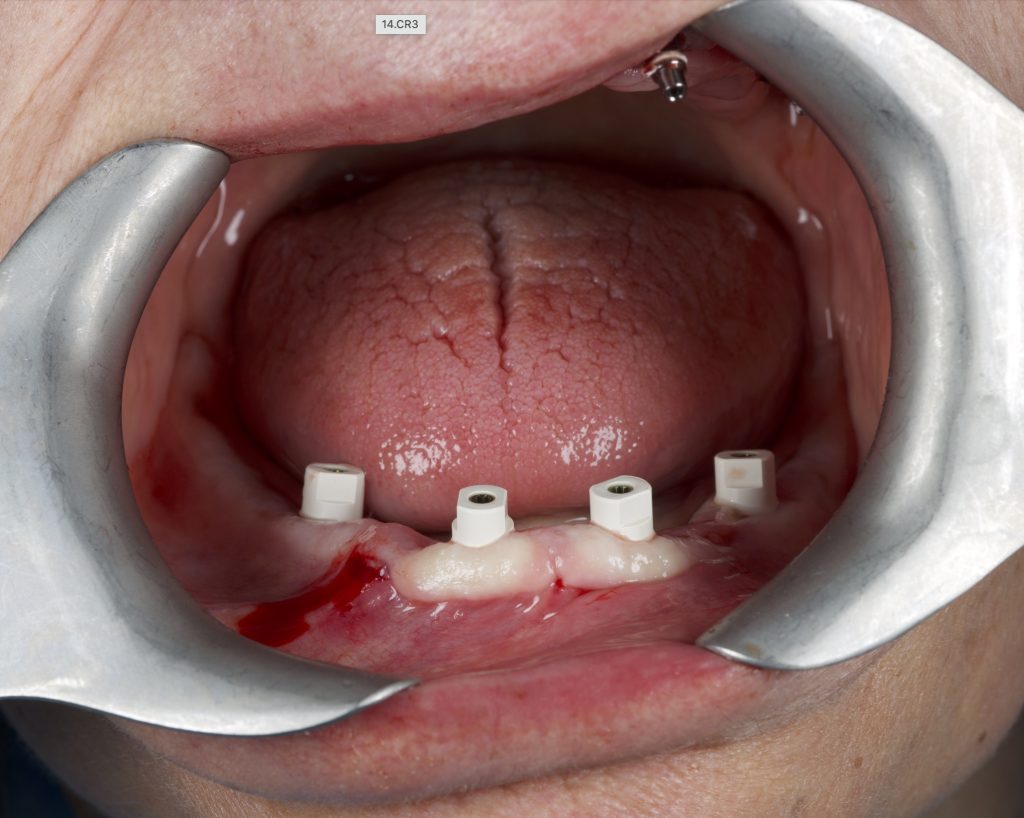

Al termine dell'inserimento implantare vengono smontati i connettori necessari per inserire lo specifico tipo di impianto e avvitati i marker sul MUA integrato per acquisire l’impronta intraorale, poi inviata con dati stl al tecnico (Figura 14).